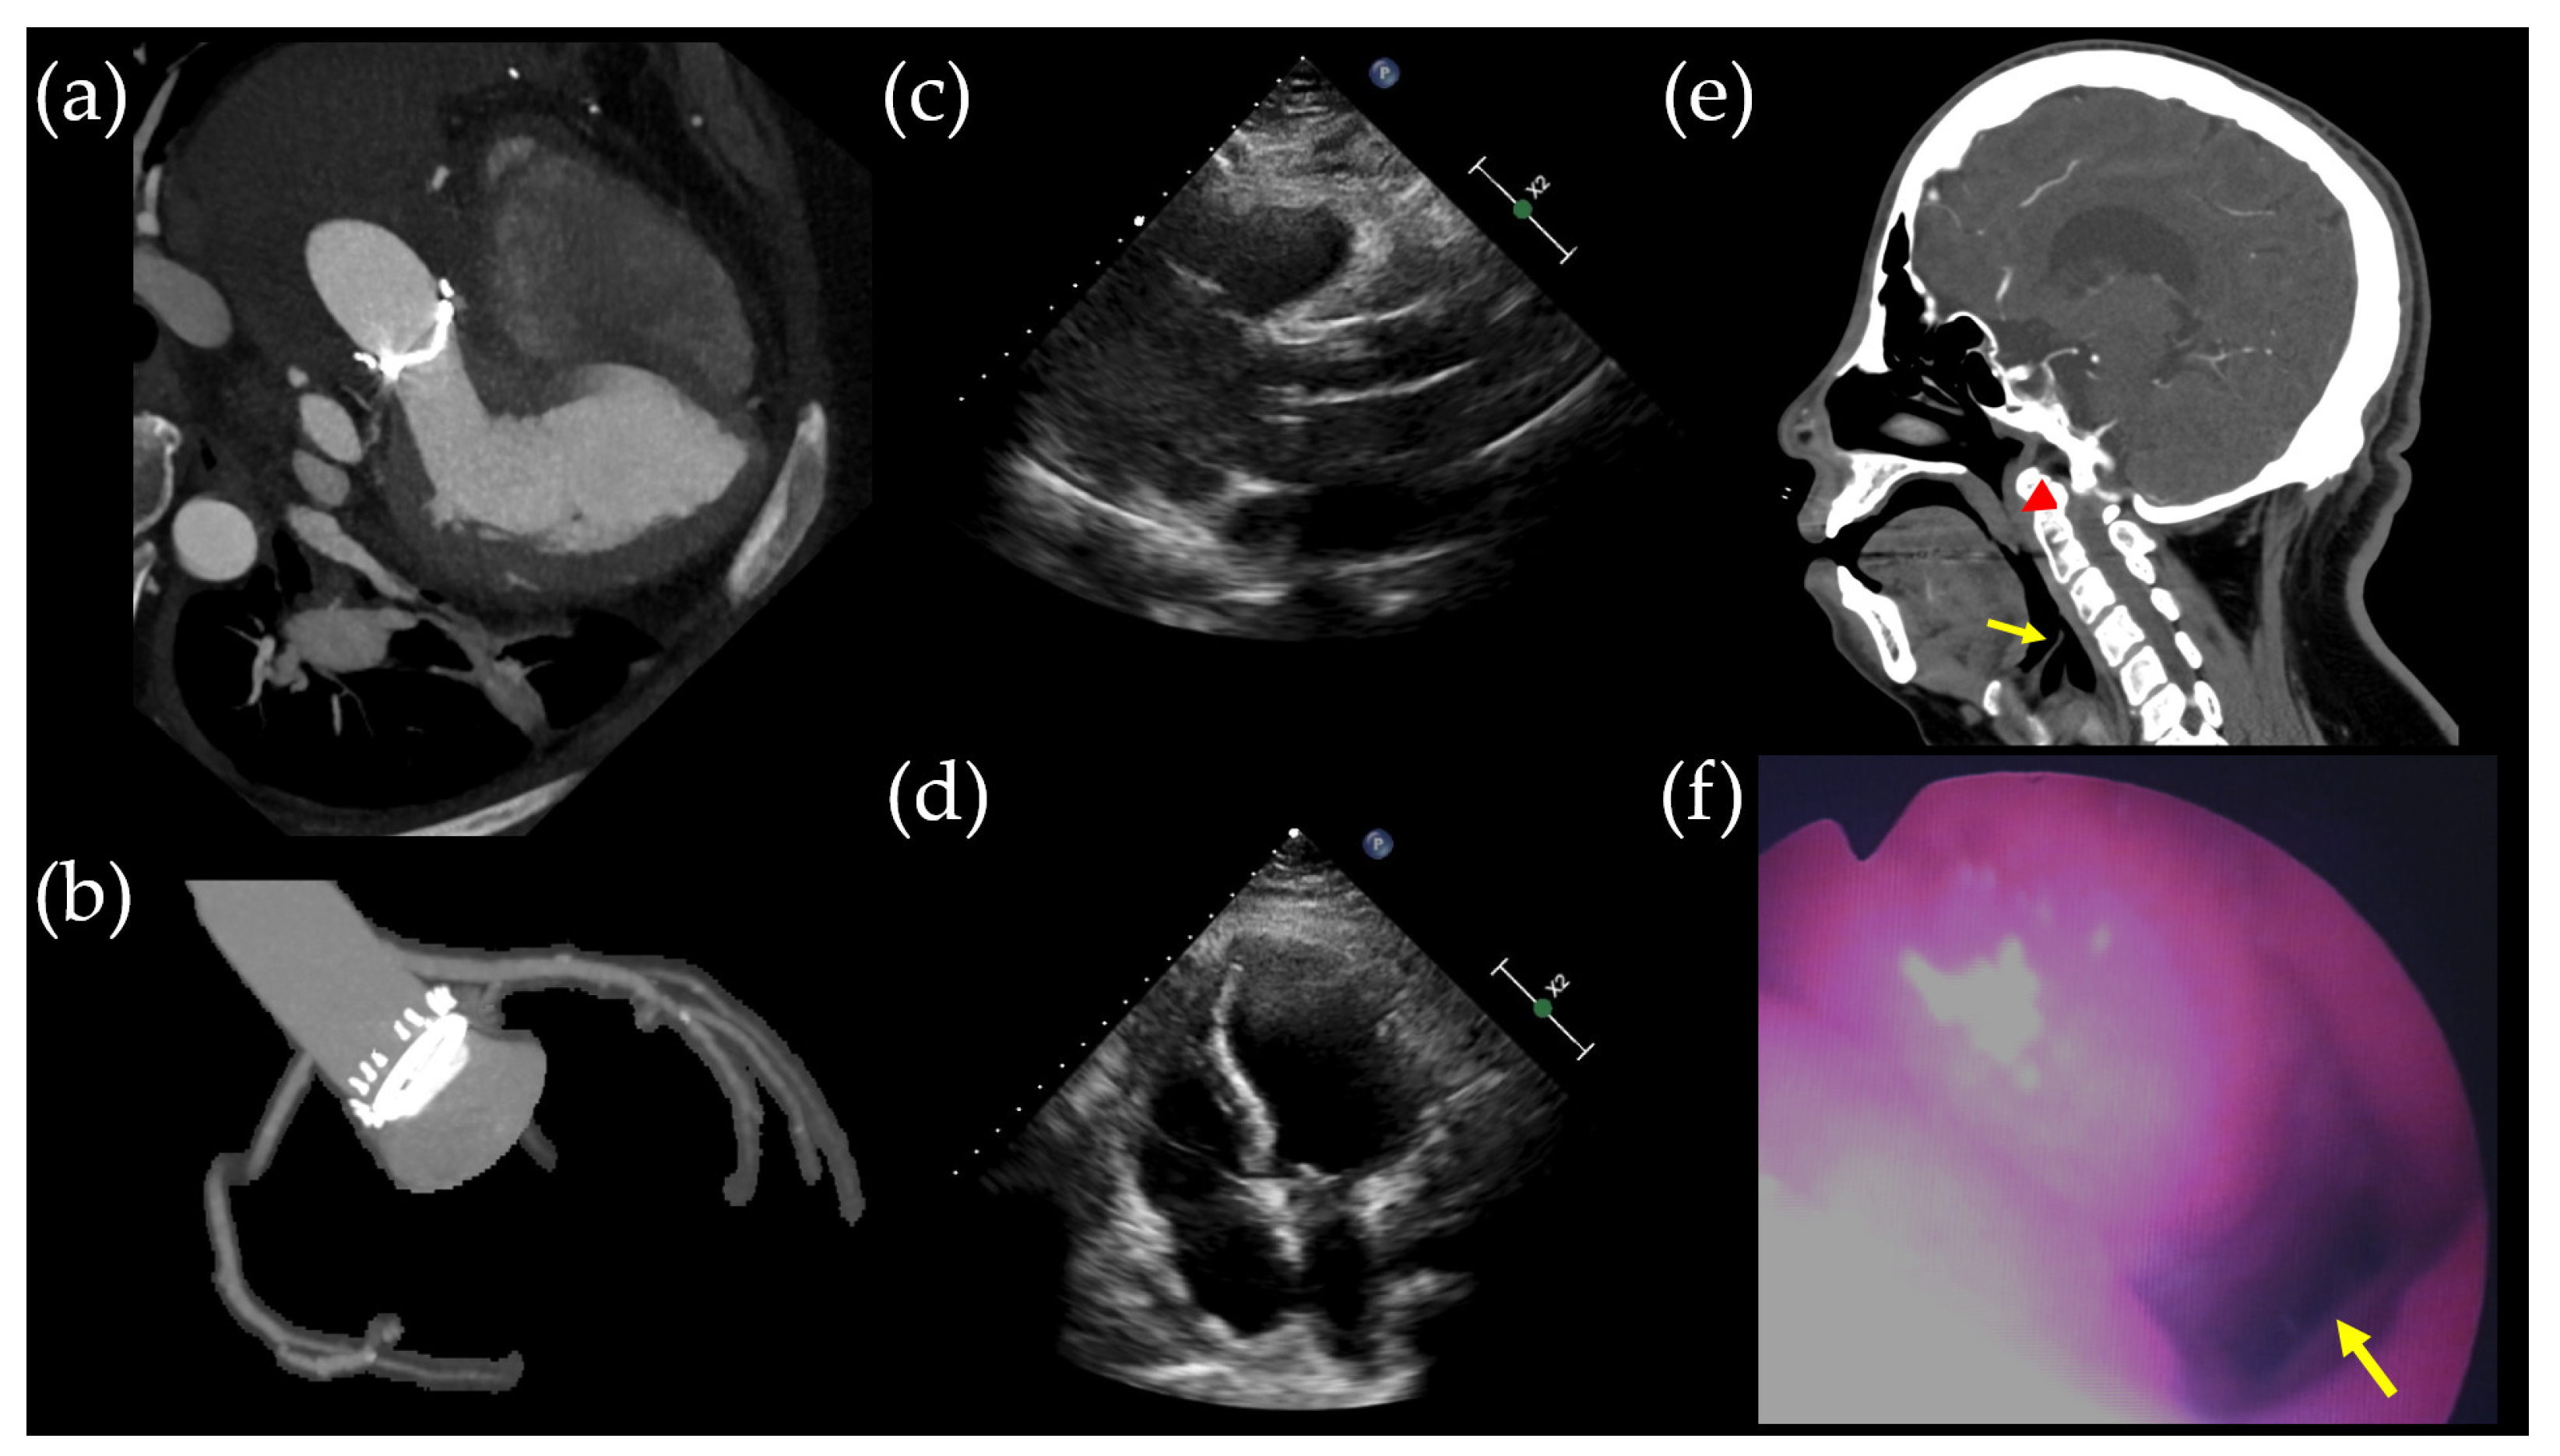

The patient’s aortic root aneurysm increased from 45 mm to 58 mm in two years, and a TRAF7 gene mutation was identified, leading to a Bentall operation. Postoperative imaging findings (Figure 3a–d) revealed improvement in dyspnea symptoms, although desaturation events persisted during sleep. Facial CT (Figure 3e) and laryngoscopy (Figure 3f) revealed narrowing extending from the nasopharynx to the oropharynx.

Figure 3. Postoperative radiologic findings. (a,b) Coronary artery computed tomography performed on postoperative day (POD) 32 illustrates the successful Bentall operation, which included aortic valve replacement (21 mm), ascending aorta replacement, and coronary button implantation. (c,d) Transthoracic echocardiogram conducted on POD 32 revealed unchanged right ventricular dilatation in size compared to the preoperative transthoracic echocardiogram. Facial CT scan (e) and laryngoscopy (f) identified narrowing of the nasopharynx and oropharynx due to a retropositioned mandible, with the epiglottis indicated by the yellow arrow and the uvula by the red arrowhead.